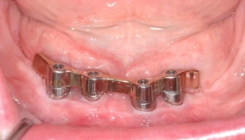

Since 1992, titanium screw implants have been inserted in edentulous sections of the upper and lower jaw in the clinic. Such dental implants serve as artificial tooth roots which, in combination with a tooth-crown-like superstructure (superstructure), enable the restoration of isolated tooth gaps with a crown, in the case of several missing teeth with a crown block, and finally in the case of an edentulous jaw with a fixed prosthesis.

In accordance with the patient's ideas and wishes, conceivable implant-supported prosthetic solutions are presented. In detail, the necessary surgical procedures are explained, the different healing times in the upper and lower jaw are pointed out and, if necessary, the possible later implant-supported dentures are described in consultation with the dentist in charge.

One of the prerequisites for a successful and durable implant restoration is sufficient height and width of the remaining jaw bone. A special focus of the clinic is to create a favorable implant site for implantation by depositing autologous bone or bone substitute materials in the maxilla by introducing the bone into the maxillary sinus.